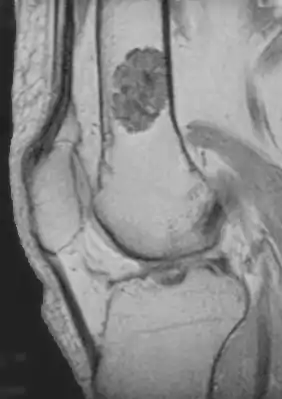

| MRI T1 showing an enchondroma in the femur | |

Diagnosistic tests include medical imaging.[2] Appearances on X-ray show a small lobe-shaped, dark tumor in the middle of the bone.[2] It typically contains white spots; calcified chondroid matrix (a "rings and arcs" pattern of calcification).[2] It does not extend into soft tissues.[6] Magnetic resonance imaging (MRI) and CT scan may be requested to further evaluate the tumor.[8]